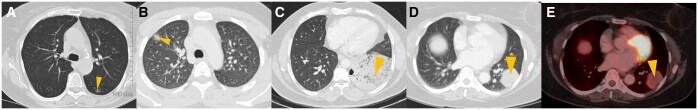

Lung cancer is the second most commonly diagnosed cancer worldwide. In the present era of targeted therapy for various lung cancer mutations, it is essential to be aware of the imaging correlates of various lung cancer mutations on contrast enhanced computed tomography of thorax. In this article, we have discussed the imaging patterns of various types of lung cancer including different mutations and also comprehensively reviewed the imaging recommendations (National Comprehensive Cancer Network [NCCN], European Society of Medical Oncology [ESMO] and American Society of Clinical Oncology [ASCO]) and management guidelines of lung cancer (non-small cell, small cell and other neuroendocrine tumours). We have also discussed guidelines for screening, diagnosis, staging (recent 9th edition tumour node metastasis [TNM]), treatment response evaluation, and follow up. Role of interventional radiology in the treatment of primary lung cancer, lung metastasis, and management of posttreatment complications, have also been described in detail in this article. In addition, current status of artificial intelligence in lung cancer has also been briefly discussed.

肺癌是全球第二大常见的确诊癌症。在当前针对各种肺癌突变进行靶向治疗的时代,了解胸部对比增强计算机断层扫描上各种肺癌突变的影像学关联至关重要。在本文中,我们讨论了包括不同突变在内的各种类型肺癌的影像学模式,并全面回顾了肺癌(非小细胞、小细胞和其他神经内分泌肿瘤)的影像学建议(美国国立综合癌症网络 [NCCN]、欧洲医学肿瘤学会 [ESMO] 和美国临床肿瘤学会 [ASCO])及管理指南。我们还讨论了筛查、诊断、分期(最新第9版肿瘤淋巴结转移 [TNM])、治疗反应评估和随访的指南。本文还详细描述了介入放射学在原发性肺癌治疗、肺转移以及治疗后并发症管理中的作用。此外,还简要讨论了人工智能在肺癌方面的现状。